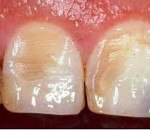

В начальной стадии происходит потеря блеска эмали в области ограниченного участка вестибулярной поверхности зуба. На данном этапе заметить признаки начавшегося эрозивного процесса можно только после высушивания поверхности зуба струей воздуха или нанесения на участок поражения 5% йодной настойки - в этом случае происходит желто-коричневое окрашивание участка эрозии.

Первоначально эрозивный дефект представляет собой округлый или овальный очаг чашеобразной формы с твердым, гладким и блестящим дном. По мере расширения и углубления очага может происходить полная утрата эмалевого слоя и обнажение дентина. При I и II степени эрозии зубов дефект имеет белесоватый цвет; при III степени патологического процесса появляется светло-желтая или коричневая пигментация.